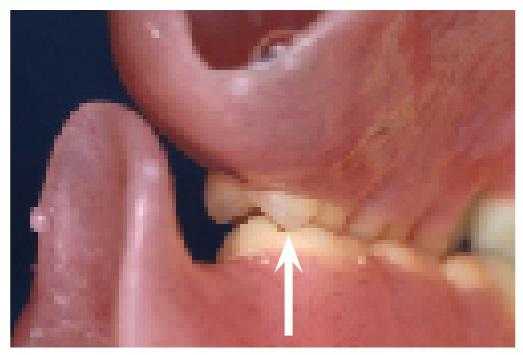

Фото 1. Пациент с дефицитом костной ткани, ограничивающим возможность установки имплантатов.

На фото 13 изображен случай соотношения гребня по 3 классу со значительной потерей костной ткани на верхней челюсти, как раз напротив нижнего протеза, фиксированного на локаторах. На фото 14 видно, что окклюзионный контакт ограниченный только задними зубами. На фото 15 изображена ситуация с обширной потерей кости на обеих челюстях.

Фото 13. Соотношение челюстей по 3 классу. Резорбированный гребень нижней челюсти с установленными абатмент-локаторами.